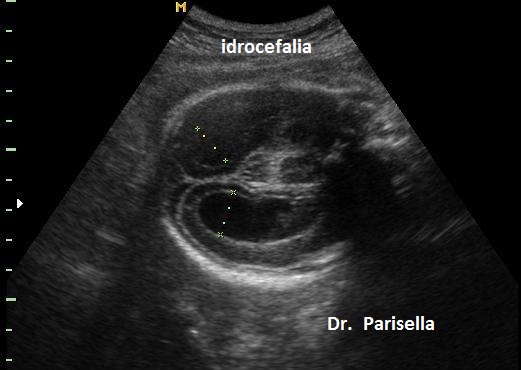

-         Anomalie del SNC: lipoma del corpo calloso, idrocefalia, malformazione di Chiari, encefalocele, ipoplasia del verme cerebellare, megacisterna magna, ipoplasia unilaterale del cervelletto.